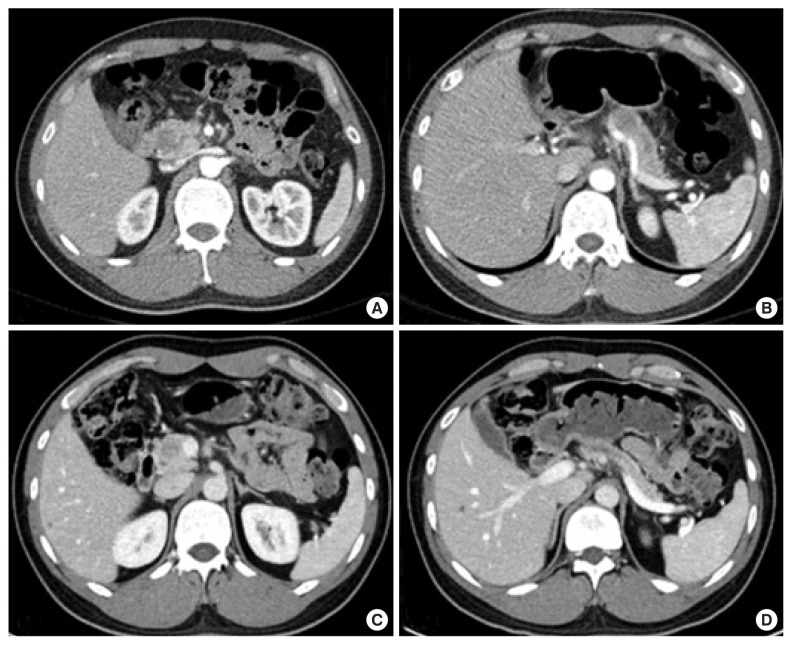

This study shows a case of neoadjuvant chemotherapy application for the management of a 34-year-old male patient diagnosed with invasive intraductal papillary mucinous neoplasm (IPMN), for which curative margin-negative resection initially seemed challenging. Five cycles of the FOLFIRINOX regimen (5-fluorouracil, leucovorin, irinotecan, and oxaliplatin) were administered preoperatively, resulting in a significant reduction of the intraductal mass size and deformity of the main vessels. The patient subsequently underwent a successful robotic pylorus-preserving pancreatoduodenectomy. Postoperatively, the patient received adjuvant chemotherapy with FOLFIRINOX, and after 5 months, showed no signs of tumor recurrence or specific complications. These findings suggest that neoadjuvant therapy can be a potentially effective strategy even in advanced invasive IPMN. Further research is necessary to establish guidelines for its application.